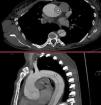

A 47-year-old woman with a past medical history of bicuspid aortopathy in her paternal grandfather; her parents died young in a traffic accident. Due to palpitations, the outpatient echocardiogram performed revealed the presence of a dilated ventricle with a left ventricular end-diastolic diameter of 71mm, indexed 3.4mm/m², left ventricular ejection fraction of 55–60%, in addition to a bicuspid aortic valve with fusion between the right and left coronary cusps that triggered severe aortic regurgitation (Fig. 2) with an aortic root of 40mm. A computed tomography scan was requested for preoperative study (Fig. 1), which was performed 3 weeks later, evidencing a Stanford/DeBakey type A aortic dissection I with an intimal flap at root level that extended longitudinally (Fig. 3) and spirally towards the left common iliac artery, involving the right brachiocephalic trunk without compromising its flow. In light of these findings, the patient was transferred to the cardiac intensive care unit for emergency surgery, undergoing David surgery with independent reimplantation of the brachiocephalic trunk.